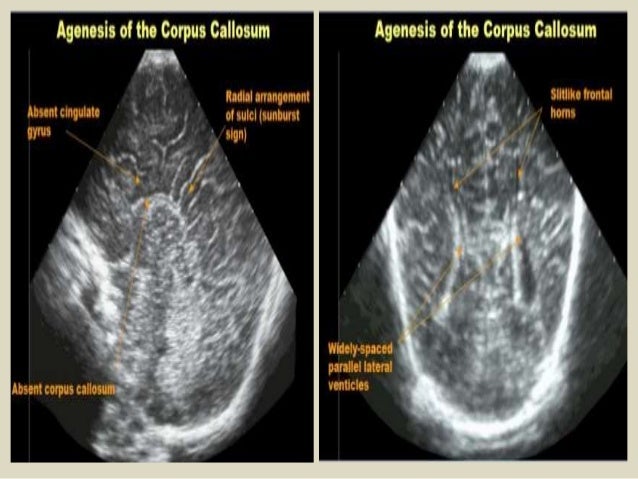

29. 29. Coronal section - Absent corpus callosum, widely separated frontal horns of lateral ventricles, dilation and posterosuperior displacement of third ventricle. Partial agenesis corpus callosum.

45. 45. Coronal and parasagittal USG demonstrating colpocephaly in a patient with agenesis of corpus callosum. Also, there is hypoplasia of the cerebellum, mainly involving the right lobe